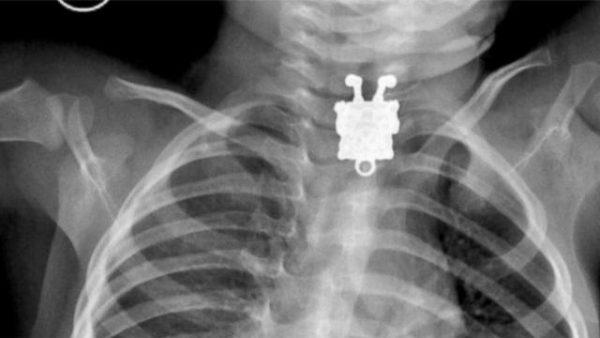

Игрушка, которую случайно проглотил ребенок